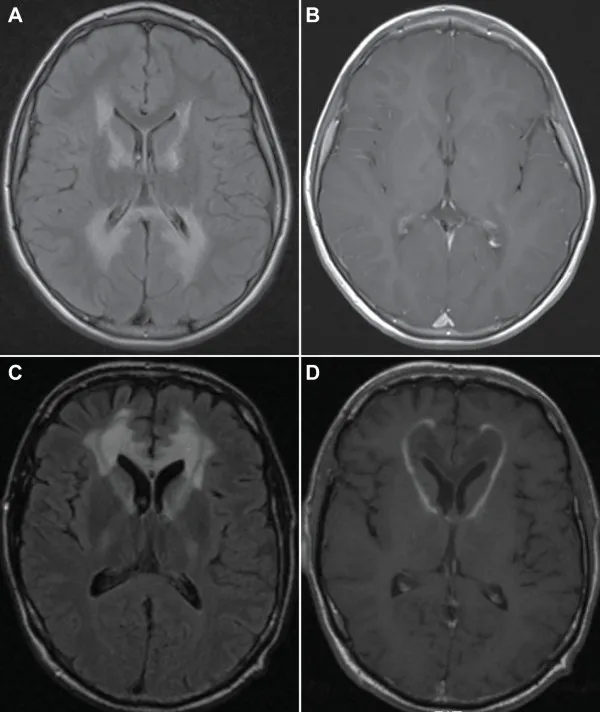

MRI検査での脳白質の評価

磁気共鳴画像(MRI)検査は、副腎白質ジストロフィー(ALD)の診断および進行評価において最も重要な画像検査の一つです。

ALDの特徴である脳白質の異常を詳細に観察できるため、早期診断や治療方針の決定に不可欠です。

ALDの患者では、MRI検査で白質病変(脱髄)が確認されることが多く、特に小児大脳型ALDでは顕著な異常が認められます。

MRI検査では、この白質の脱髄を視覚的に評価できます。

- 後頭葉・側頭葉の白質病変(小児大脳型ALDに多い)

- 脳梁の萎縮(神経機能の低下を示唆)

- 進行すると前頭葉にも拡大し、重度の神経症状を引き起こす

ALDのMRI画像の特徴

ALDのMRI画像では、以下のような特徴的な所見が見られます。

- T2強調画像:白質病変が高信号(白く映る)

- FLAIR画像:後頭葉や側頭葉の病変がより明瞭に観察される

- 造影剤(ガドリニウム)使用時:病変部の炎症を評価可能

www.researchgate.net/figure/MRI-of-the-brain-in-a-case-of-childhood-cerebral-ALD-showing-characteristic-extensive_fig1_230664734%5B/caption%5D

この領域は脳性ALDの約80%の症例で最初に侵される。

ガドリニウムを投与するとT1画像で縁が強調される(B)。

約20%の症例では脳性ALDの初期病変部位が前頭部白質であり、別の脳性ALD患者のFLAIR像(C)に示すように、

T1強調像(D)でガドリニウム投与後に顕著な縁の増強がみられる。

出典:ResearchGate